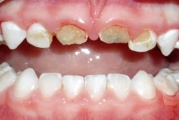

Tetratsükliini liigtarbimise tõttu värvunud hambad

Fluoroos

Fluoroosi

Hammaste defektid

Emaili hüpoplaasiad